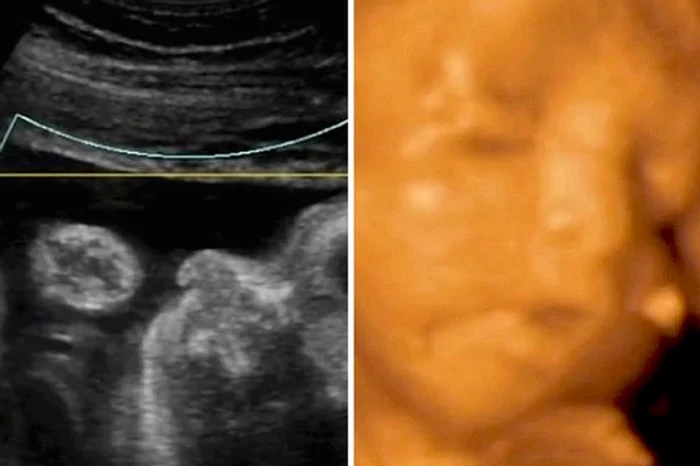

Difereța uimitoare dintre ecografia 3D și cea 4D provoacă emoție oricărei mame înainte de a naștefoto: mirorr.uk.co

Ecografia 4D dezvăluie ce se întâmplă cu un copil în burtica mamei. Aceasta poate surprinde cum bebelușul nenăscut mănâncă, plânge sau strănută. Medicii au studiat îndeaproape tot comportamentul copilului, pe toată durata celor nouă luni de sarcină.

Imagini uluitoare surprinse de ecografia 4D

Copilașul, botezat Pat Lambert, dormea ​​în momentul realizării acestei ecografii, astfel că soția lui Alexander a fost nevoită să facă puțină mișcare. Ecografia a surprins cum copilul își freacă ochișorii și arată o față tristă, deoarece a fost trezit din somn. Aceasta nu este singura reacție captată de 4D. Atunci când mama a mâncat și a băut, reacția copilului a șocat pe toată lumea. Ecografia imortalizează momentul în care micuțul se strâmbă atunci când este nevoit să mănânce.